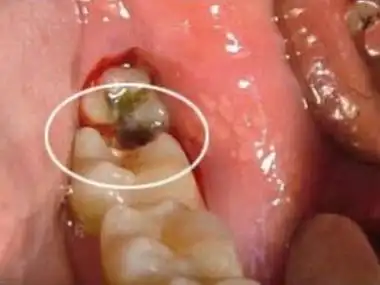

第二磨牙成了龋齿,都已经烂空了是该拔掉还是补一补就可以了?

什么原因引起如此严重的龋齿

图18-9 s-ecc儿童广泛的右下第二乳磨牙龋坏及尚未完全萌出的右下第一